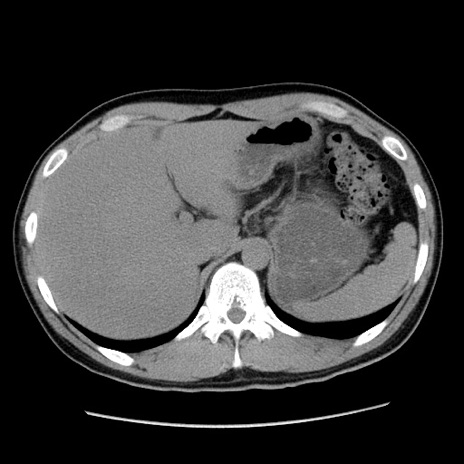

症例36(横断像)

【症例】20歳代 男性

【主訴】心窩部痛

【現病歴】今朝より上腹部痛あり。一旦軽快していたが再度出現したため救急要請。昨日夕に白身の魚を含む刺身を食べた。

【身体所見】BP 136/89mmHg、HR 74/min、BT 37.0℃、腹部:膨満、軟、心窩部に圧痛あり。反跳痛なし、筋性防御なし、腸雑音やや亢進あり。

【データ】WBC 17700、CRP 0.48